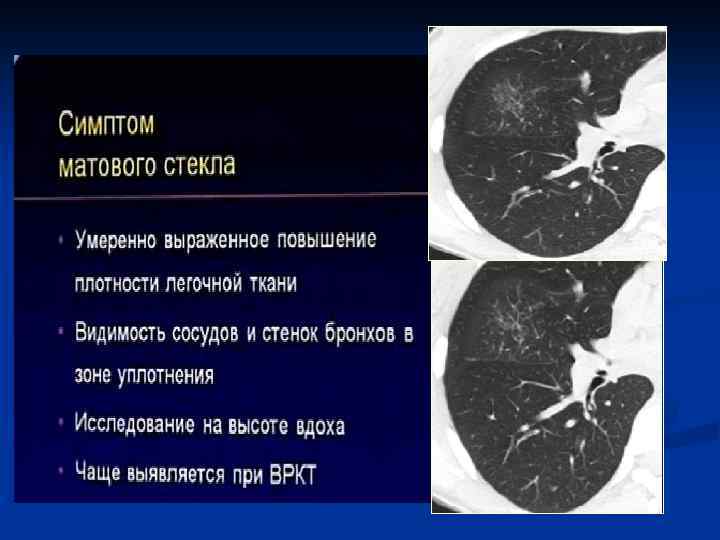

КТ-семиотика интерстициальной пневмонии n n n Понижение прозрачности легочной паренхимы по типу «матового стекла» Утолщение внутридолькового интерстиция Утолщение междолькового интерстиция Утолщение перибронховаскулярного интерстиция Тракционные бронхо- и бронхиолоэктазы Изменения по типу «сотового легкого»